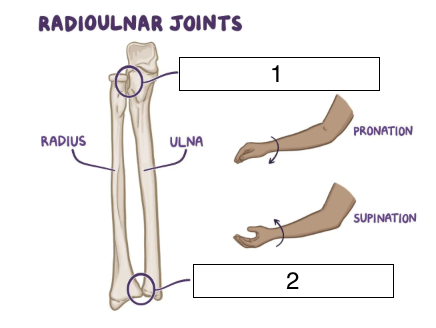

what is the highlighted joint (number 1)?

proximal radioulnar

what is the highlighted joint (number 2)?

distal radioulnar

what kind of joints are the proximal and distal radioulnar joints?

synovial, pivot joint